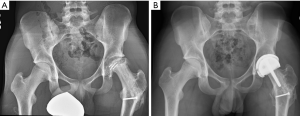

There have been few femoral component failures. Such failures are related to the fundamental health of the femoral head. Femoral components can be cemented yet, more recently, cementless fixation is performed and is an attractive option. The femoral component can be anatomic or flat topped (Figure 3). The author has had good success with a cementless anatomic femoral component. Ceramic-coated implants are attractive from a wear standpoint and they are appealing to patients who have concerns about reactions to implanted metals (33).

Methods

Twenty-four patients (1%) underwent successful revision of their femoral component to a stem-supported implant from 3 to 20 years following the initial surgery. The causes of failure were femoral neck fracture (12), femoral loosening or subsidence (9), and infection (3). Two patients had a revision of their femoral resurfacing component to another femoral resurfacing component. In all revisions, the metal-backed acetabular component was retained and the acetabular liner was exchanged to allow use of a smaller or the same highly cross-linked polyethylene. There were five acetabular revisions for loosening. A new shell with screw fixation resulted in a secure component and successful outcome. Using revision for any reason as the endpoint, the Kaplan-Meier survival estimate of mean survivorship was 97.5% (95% CI, 95–98.9%) at 10 years (Figure 3). There were no bearing-surface failures or pending revisions.